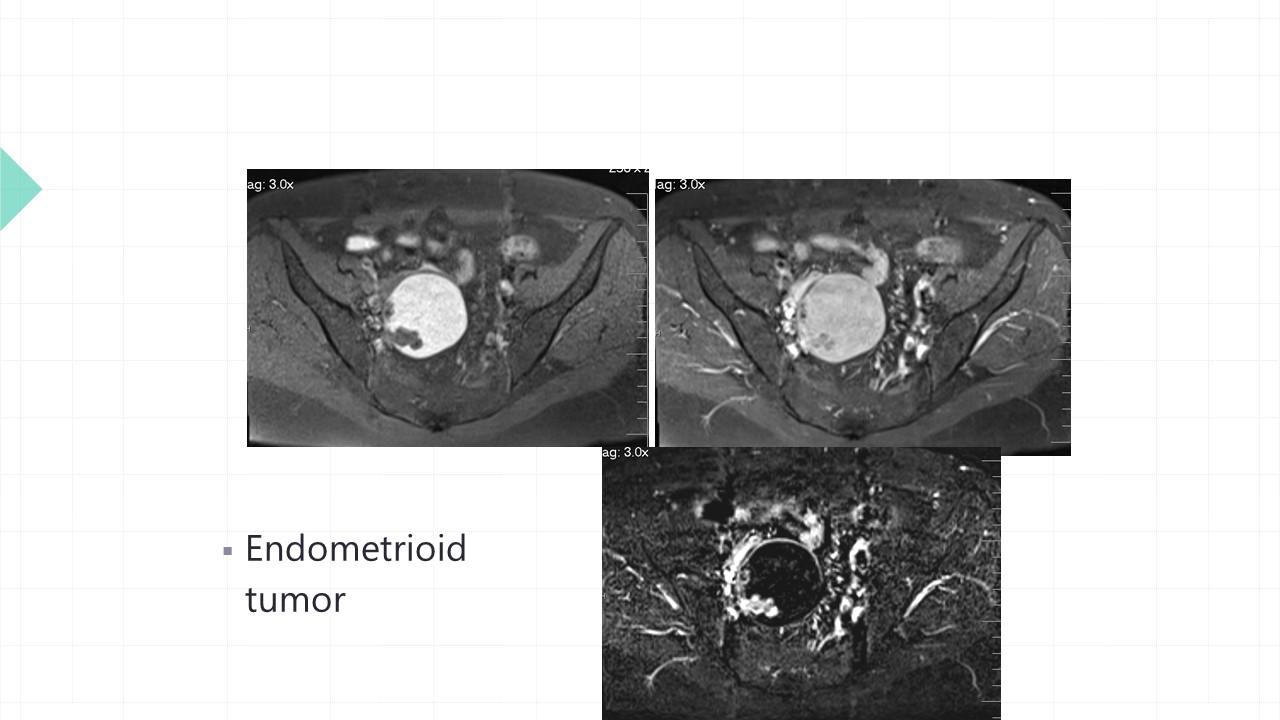

Vai trò cộng hưởng từ trong đánh giá lạc nội mạc tử cung